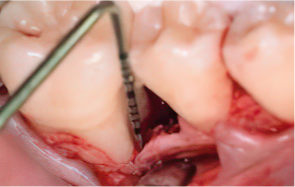

엠도게인 수술과정

-

STEP 01

잇몸을 절개

STEP 02

Scaling Root Planning을 실시

STEP 03

치석 및 치태 등 제거

STEP 04

엠도게인 도포

STEP 05

클렌징

STEP 06

판막을 봉합